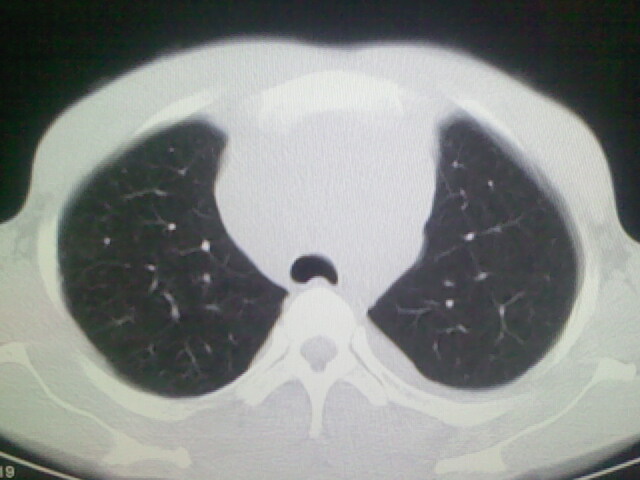

以下是引用杀毒软件在2008-9-3 6:11:00的发言:[br]侵袭性胸腺瘤------一般不侵到气管旁[br][br]考虑----纵隔淋巴瘤,心包及胸膜受累

以下是引用随光逐影在2008-9-3 7:07:00的发言:[br]1)考虑淋巴瘤可能。2)双侧胸腔积液(以左侧为甚)。3)心包积液。